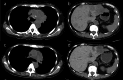

Pseudoprogression, a transient radiographic flare caused by immune infiltration, is common after immune-checkpoint inhibitors but has not been reported with tarlatamab, a bispecific T-cell engager approved for third-line small-cell lung cancer (SCLC). A 57-year-old woman with extensive-stage SCLC and syndrome of inappropriate antidiuretic hormone secretion (SIADH) received tarlatamab. Within hours, she developed bone pain; Day 7 imaging showed marked tumour swelling and pleural effusion despite negative cytology and rising serum sodium. Therapy continued. By Day 13, computed tomography demonstrated regression of thoracic and hepatic lesions and falling pro-gastrin-releasing peptide (pro-GRP). Early pseudoprogression and paraneoplastic biomarker improvement may predict efficacy.